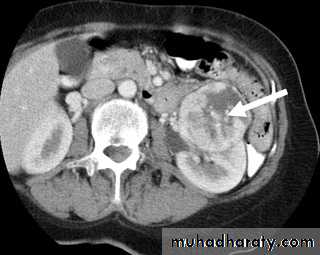

CT SCAN RT sided Renal cell ca.